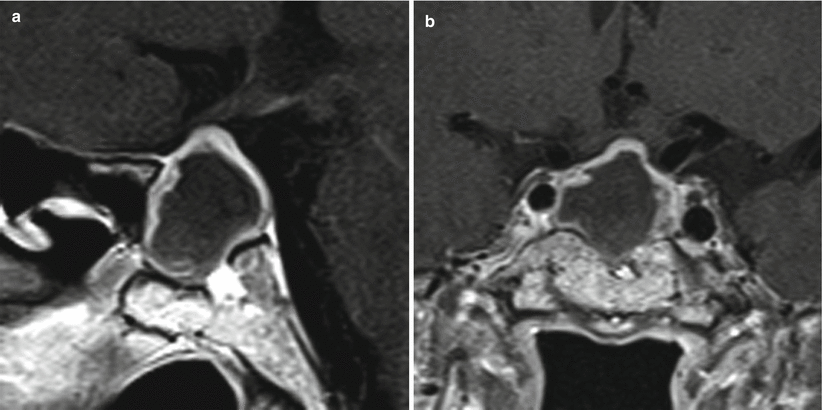

Rathke cleft cyst: 3.0-t sagittal t1-weighted image (t1wi) (a) and t2wi ...Histopathological study indicative of rathke's cleft cyst. above: a Clinical characteristics of patients with rathke's cleft cystRathke cleft cyst.

A 24-year-old woman with Rathke's cleft cyst. There is a... | Download